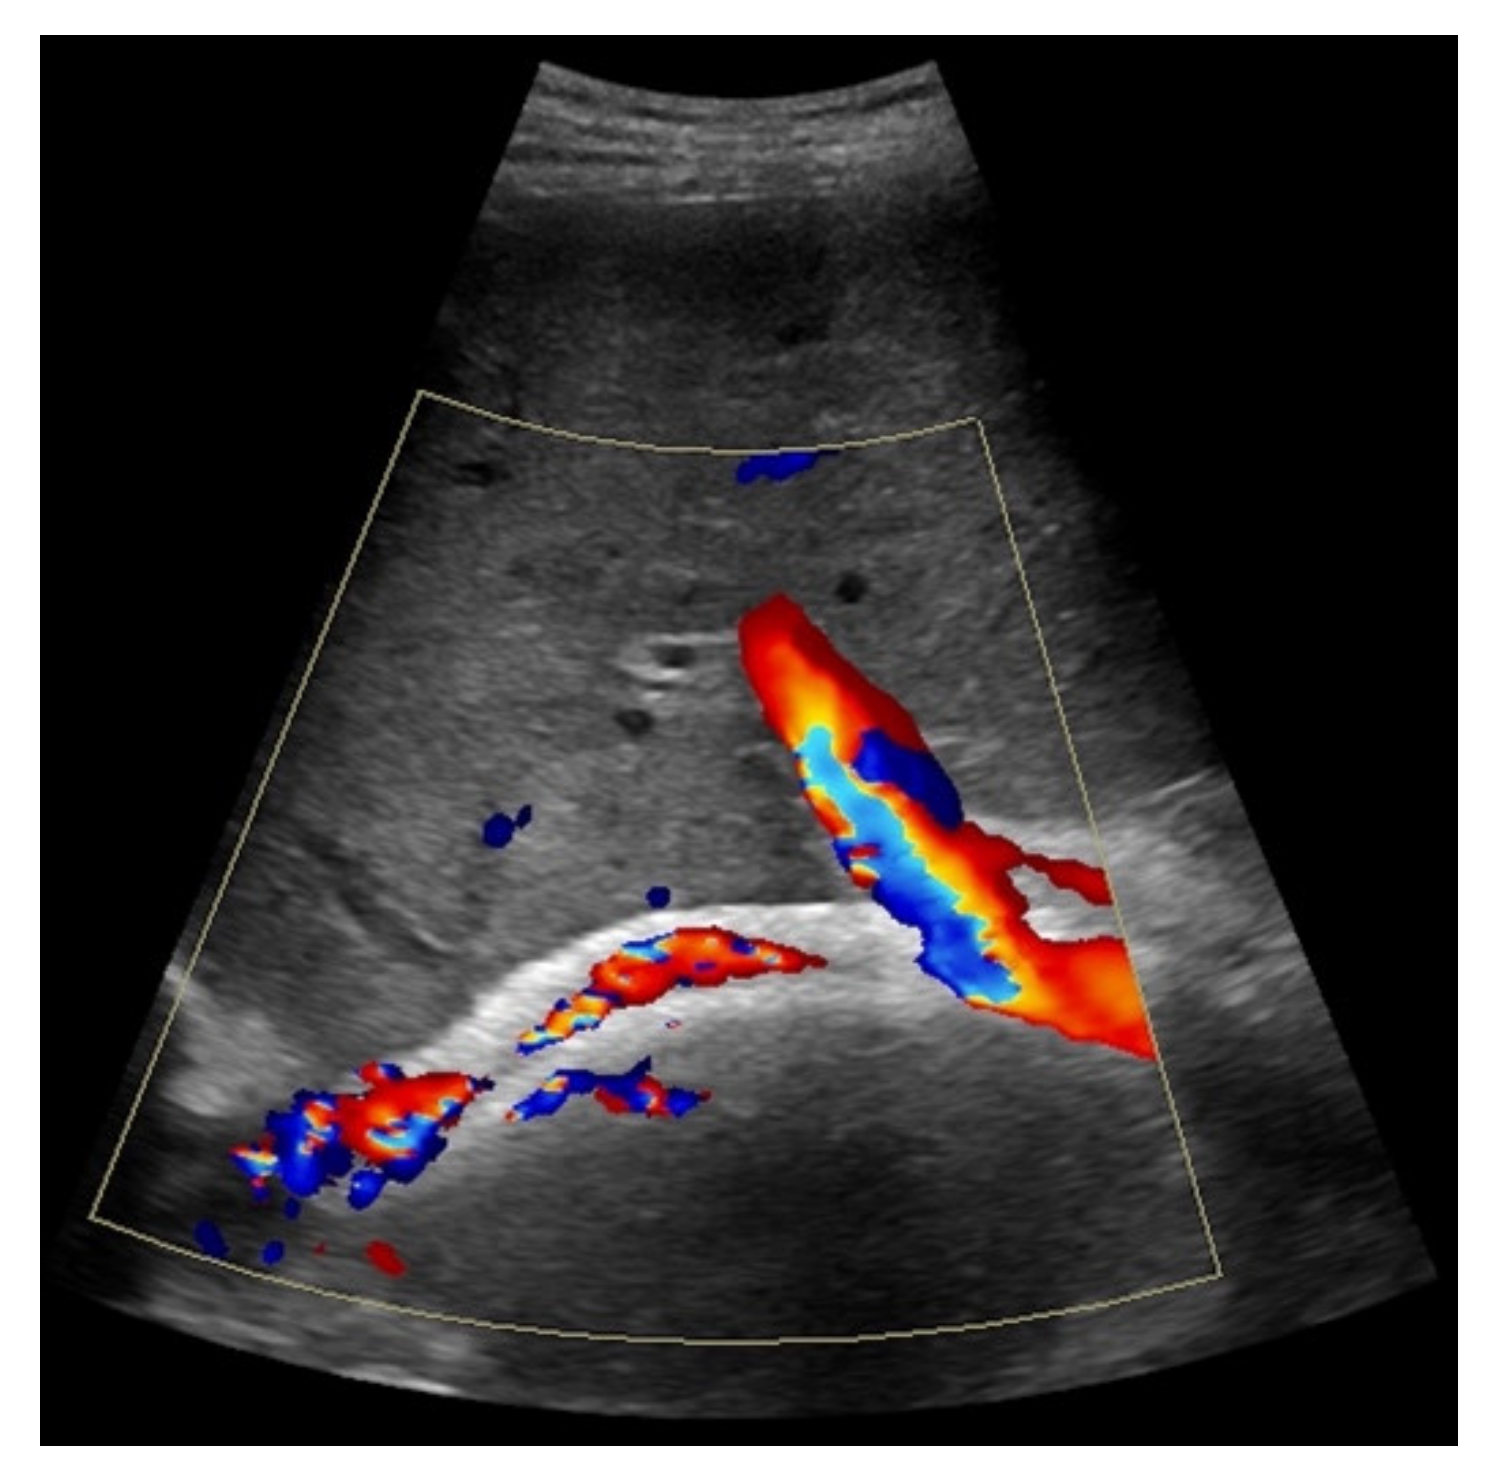

When taking a closer look at the results of the CEUS examinations, 70.8% (n = 75) of the patients showed regular stent perfusion (Figure 4), 17.9% (n = 19) of the patients featured TIPS occlusion (Figure 5) while 6.6% (n = 7) patients had stent thrombosis (Figure 6). In contrast to the results from CDUS, there were no patients with only partial accessibility of the TIPS during CEUS, while the two patients with meteorism also were not assessable during CEUS. The three patients categorized in “others” showed simultaneous findings between CDUS and CEUS (Table 2).

Considering findings from CDUS and CEUS examination, in eight patients results were inconsistent (7.6%). Five patients who were only partially assessed via Color Doppler ultrasound showed a regular perfusion by using CEUS (Figure 7), two patients in whom inconspicuous TIPS perfusion was registered by CDUS showed partial occluding stent thrombosis by CEUS while in one patient suspected stent thrombosis in CDUS could not be verified by CEUS (Table 3).

Figure 7. 52-year-old female patient with irregular presentation of the transjugular intrahepatic portosystemic shunt (TIPS) on B-mode ultrasound (a) and partial flow on Color Doppler ultrasound (CDUS) (b). After contrast administration, in contrast to CDUS, regular and continuous contrast of the TIPS is seen without evidence of thrombotic alterations or occlusion (c).